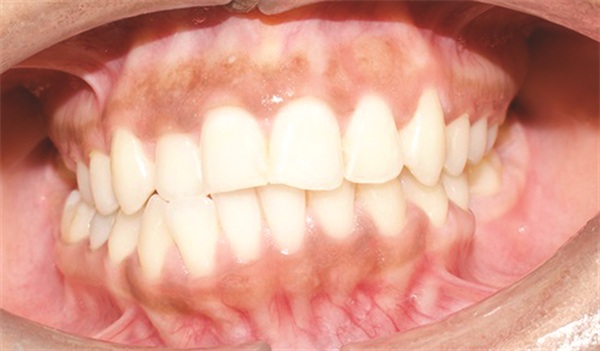

The diagnostic findings told a more complicated story. The patient presented with a skeletal Class II relationship, bilateral Class I molar and canine relationships, collapsed arches, and proclined incisors in both arches. Both midlines were shifted to the right. She also exhibited crossbite of the upper right first molar and upper right lateral incisor, a discrepancy between centric relation and centric occlusion, and a noticeable cant in the lower anterior segment. Her dental history included previous extractions of the upper right third molar and upper left second molar (Figs. 1–12).

Fig. 1